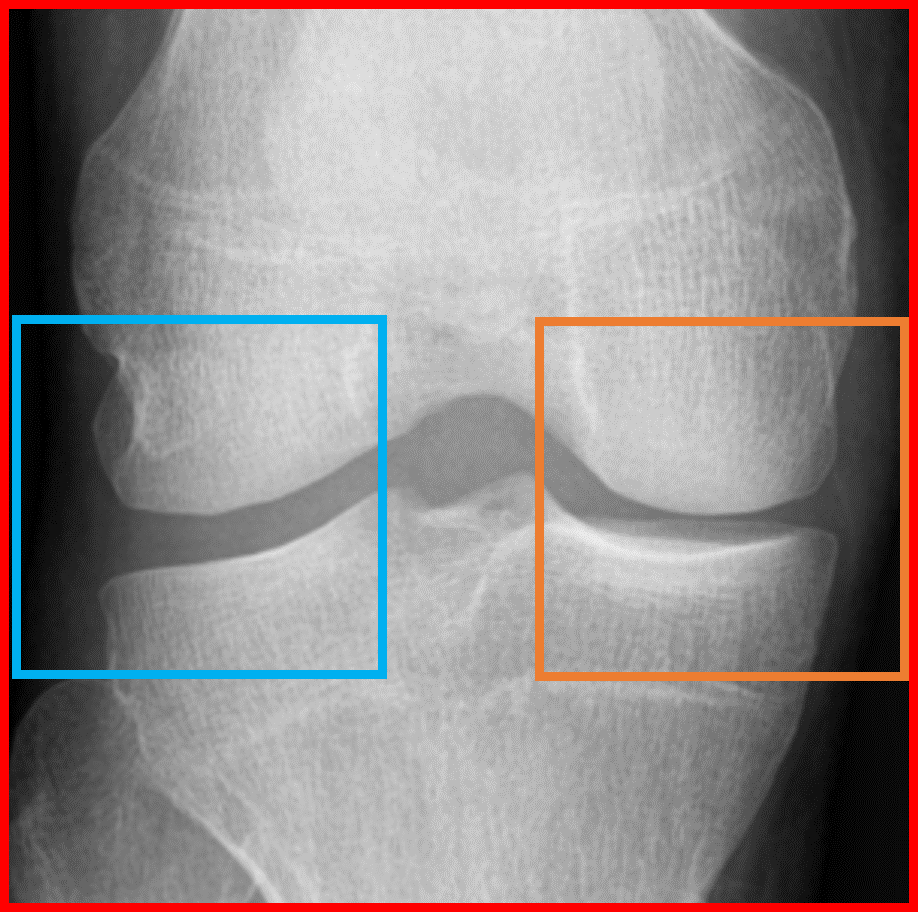

Since the aim of this study is the early detection of knee OA (KL=0 vs. KL=2), we focused on the characteristics of the lateral and medial sides of the knee joint. We used the same ROIs as [chen] available at put a reference for the link. ROIs were extracted from the original X-ray images using YOLOv2 [yolov2]. Then, the fully automatic segmentation method proposed in [tiuplin] to extract the patches was used. Firstly, two 128×\times×128 pixel square patches were cropped from the left and right parts of the knee joint to cover the whole distal area. Secondly, the patch from the medial side was flipped horizontally. Finally, the two patches were used as inputs of the learning model.

Refer to caption

Figure 3: (a) Original knee radiographs from OAI, extracted ROI in red. (b) Obtained patches in blue and orange boxes. (c) Extracted patches for the two sub-networks respectively